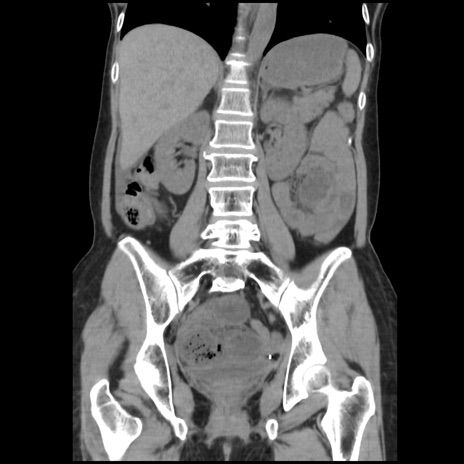

症例32(冠状断像)

【症例】40歳代 女性

【主訴】上腹部痛、嘔気・嘔吐

【現病歴】約9時間前頃から急に上腹部痛、嘔気、嘔吐が出現。改善しないため救急要請。

【既往歴】子宮頚癌(広汎子宮全摘術、放射線療法)、腸閉塞

【身体所見】腹部:平坦、軟、腸雑音亢進、上腹部を中心に腹部全体に圧痛あり。

【データ】WBC 8400、CRP 0.03